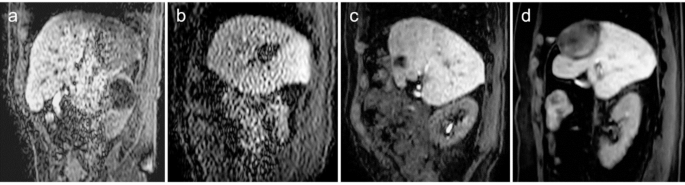

The results of the signal-to-noise ratio (SNR) and CR in the clinical study are shown in Fig. 3. For the quantitative analysis, the SNR of liver (SNRLiv) and tumor (SNRTum) were 6.8 ± 2.7 and 2.8 ± 0.8 for SENSE, 6.7 ± 2.8 and 3.0 ± 1.0 for CS without denoising (CS-no), and 14.4 ± 3.9 and 5.7 ± 2.8 for CS with strong denoising (CS-strong), respectively (P < 0.001). Cine-MRI with CS-strong demonstrated the highest SNRLiv and SNRTum with significant differences compared with cine-MRI with SENSE and cine-MRI with CS-no. On the other hand, the CRLiv/Tum was 0.47 ± 0.13 for cine-MRI with SENSE, 0.43 ± 0.12 for cine-MRI with CS-no, and 0.49 ± 0.16 for cine-MRI with CS-strong (P > 0.05). CS was able to acquire images without changing the image contrast of HBP cine MRI. Table 1 presents the results of qualitative analyses. Qualitative analysis revealed significantly higher quality images of cine-MRI with CS-strong with regards to lesion conspicuity, contrast enhancement, image noise, and overall image quality (P < 0.01) than those of cine-MRI with SENSE and cine-MRI with CS-no (Fig. 4). Notably, CS had no negative impact on motion smoothness in the visual assessment (P = 0.11). The original cine-MR images of the three different imaging sequences are available as supplemental files.

Example of clinical cine-MRI with various visual scores. (a) cine-MRI with SENSE shows poor lesion conspicuity, excellent contrast enhancement, non-diagnostic image noise, good motion smoothness, and poor overall image quality. (b) cine-MRI with CS-no shows good lesion conspicuity, poor contrast enhancement, poor image noise, poor motion smoothness, and poor overall image quality. (c) cine-MRI with CS-strong shows good lesion conspicuity, good contrast enhancement, good image noise, excellent motion smoothness, and excellent overall image quality. (d) cine-MRI with CS-strong shows excellent lesion conspicuity, excellent contrast enhancement, excellent image noise, excellent motion smoothness, and excellent overall image quality.